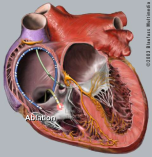

Catheter Ablation

In recent years, catheter ablation has become a standard treatment for some heart rhythm disorders, particualry supraventricular tachycardia (SVT). Wolff-Parkinson-White syndrome (WPW) and atrial fibrillation (AF). I have experience of these procedures, with an experience of >1000 cases over 16 years. Catheter Ablation

Catheter ablation procedures:

SVT

WPW syndrome

Atrial flutter and fibrillation